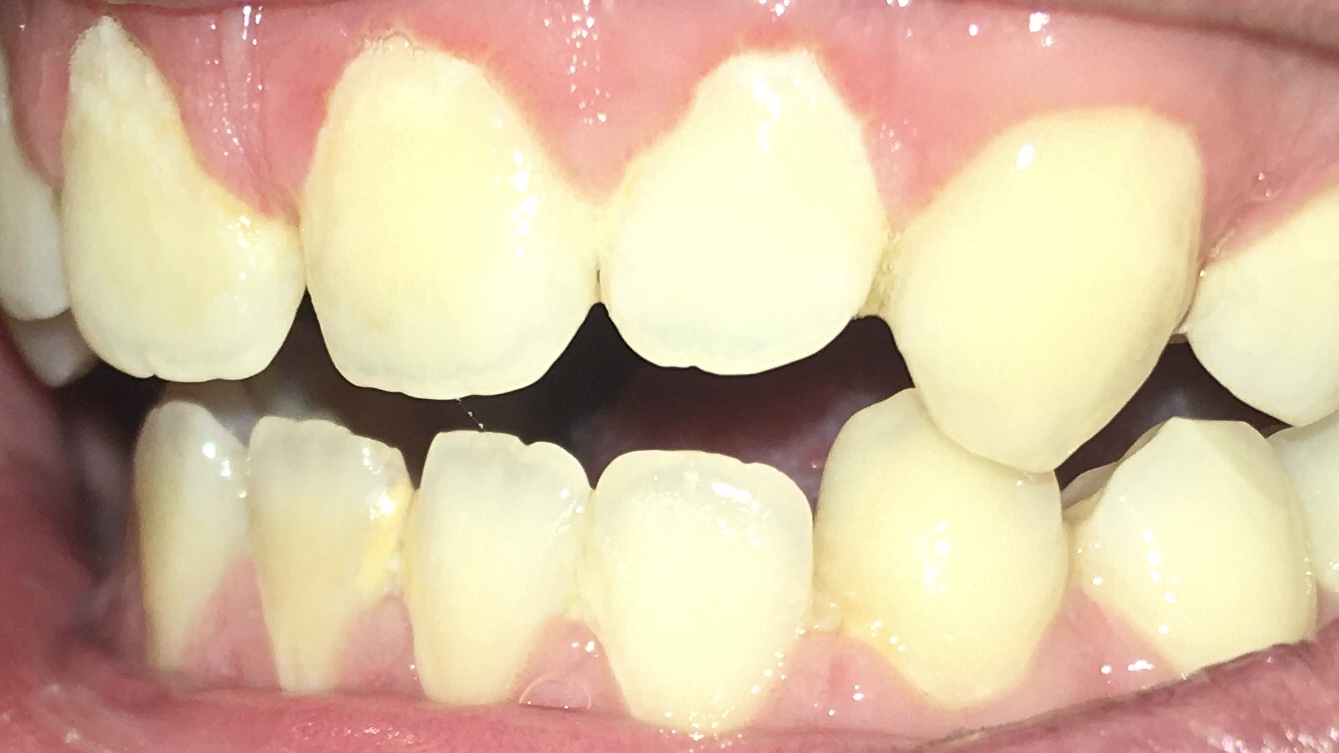

Опустились дёсны в нескольких местах, обнажились шейки зубов. Чувствительные, болят от прикосновений, могут реагировать на холодное, горячее, сладкое.

Ситуация как примерно на пик2.